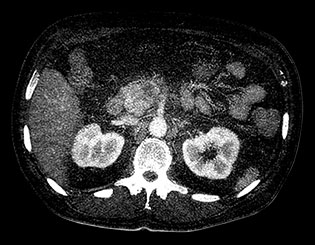

Здесь представлена серия изображений, на которых значения воксела обозначают эффективное атомное число. Эффективное атомное число может быть дробным, обозначающим какой-либо элемент, соединение или смесь. Данное число может отличаться от порядкового номера, указанного в периодической таблице. Единица для обозначения — Z.